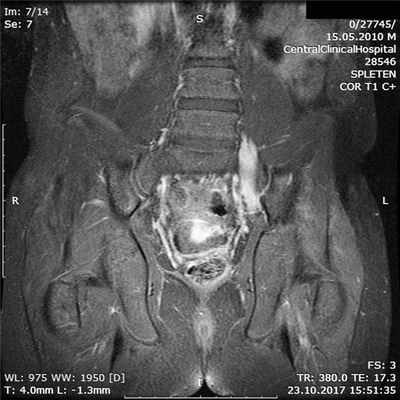

На фоне лечения отмечено значительное улучшение состояния ребенка в виде нарастания мышечной силы в левой ноге, мышцах, удерживающих левую лопатку, а также уменьшение выраженности мышечных гипотрофий (рис. 3). Рис. 3. Тот же пациент. Клиническая оценка мышечной силы на фоне иммуномодулирующей терапии через 4 мес. а — появилось тыльное сгибание стопы слева; б — сохранность силы мышц подошвенного сгибания стопы; в — регресс слабости мышц, удерживающих лопатку слева. Именно ответ на иммуномодулирующую терапию послужил фактом, подтверждающим диагноз фокальной формы ХВДП.

При очевидном улучшении состояния при повторном МРТ поясничного сплетения накопление контрастного вещества нервными стволами сохранялось (рис. 4). Рис. 4. Тот же пациент. МРТ пояснично-крестцового сплетения в режиме Т1 с контрастным усилением гадолинием на фоне иммуномодулирующей терапии через 4 мес.

Ответ на иммуномодулирующую терапию в представленном случае стал фактом, подтверждающим диагноз.